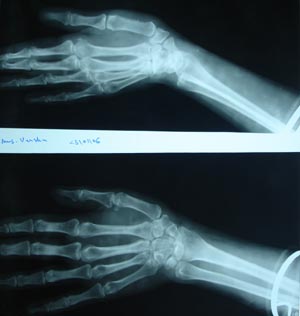

View Normal upper extremity AP & lateral view

Normal upper extremity AP & lateral view